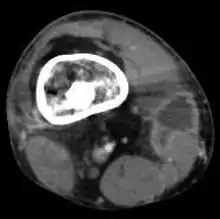

| |

| Osteomyelitis of the 1st toe | |